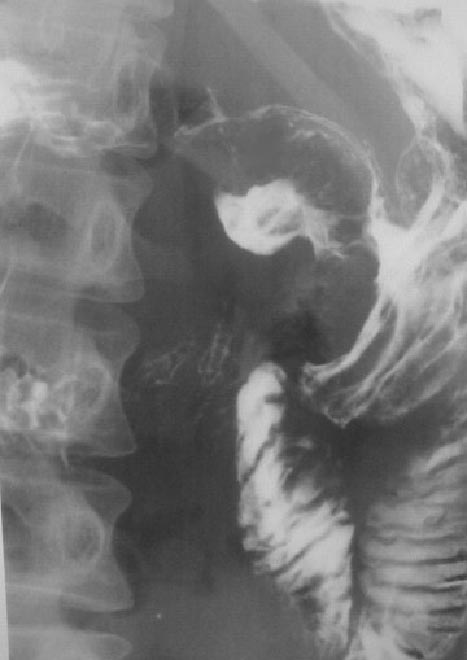

SIGNO DEL MENISCO DE CARMAN

Signo de úlcera gástrica maligna en el estudio baritado. En la proyección lateral, realizada con compresión la úlcera presenta un aspecto semicircular o meniscoide. El borde interno del contraste atrapado dentro de la úlcera es convexo hacia la luz (flecha) aunque puede ser plano, a diferencia del Signo del cuarto creciente o semiluna de las úlceras gástricas benignas en las que el borde interno es cóncavo hacia la luz. El borde externo del nicho no supera el límite esperado de la pared gástrica (marcado con la línea amarilla).

En la imagen, el signo en una paciente con adenocarcinoma de células en «anillo de sello».

Otro ejemplo del menisco de Carman.